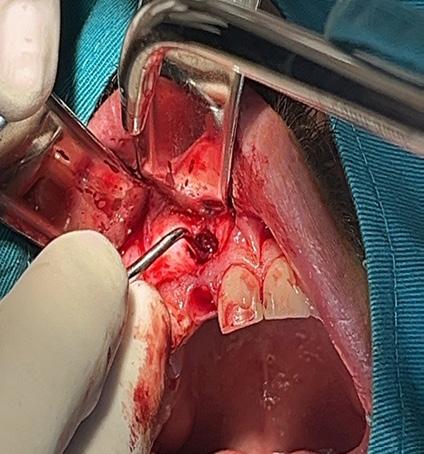

Tratamiento combinado de un quiste radicular de larga data: A propósito de un caso clínico

Combined treatment of a long-standing radicular cyst: A clinical case report

Javier BorisAdrián Burgos, Johanna Valentina Virreyra Bloomfield..........................................................133-142